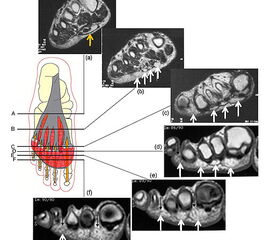

Die Plantaraponeurose besteht aus zwei Gewebeschichten. In Höhe des Metatarsaleschafts teilt sich die Plantaraponeurose in fünf kräftige Zügel, die durch Fettkörper separiert werden (Abb. 4). Weiter distal, in Höhe des Metatarsalehalses trennt sich dann die oberflächliche von der tiefen Schicht.

MRT Aufnahmen zeigen das plantare Fettpolster zwischen den beiden Schichten der Plantaraponeurose.

<div style="text-align:left">(a) In der sagitalen Schnittführung des MRTs ist erkennbar, wie die oberflächliche und die tiefe Schicht der Plantaraponeurose

Abbildung 5

Die tiefen Ausläufer spalten sich dann weiter in einen medialen und lateralen Zügel. Diese und ziehen dorsal um die Sehnenscheide der Flexoren mit Ausläufern in die plantare Platte und in die tiefen intermetatarsalen Ligamente. In diesem Bereich vereinigen sich die proximalen Ausläufer des plantaren Fettpolsters zu einer einheitlichen Struktur, die den Raum plantar der Metatarsophalangealgelenke und Grundphalangen über die gesamte Breite des Vorfußes ausfüllt. Zur Fußsohle hin begrenzt die der Haut aufliegende, oberflächliche Schicht der Plantaraponeurose das plantare Fettpolster. Distal davon zieht das Fettpolster nach dorsal und ist an den Grundphalangen, den Sehnenscheiden der Flexoren und den dazwischen liegenden Bandstrukturen fixiert (Abb. 5).